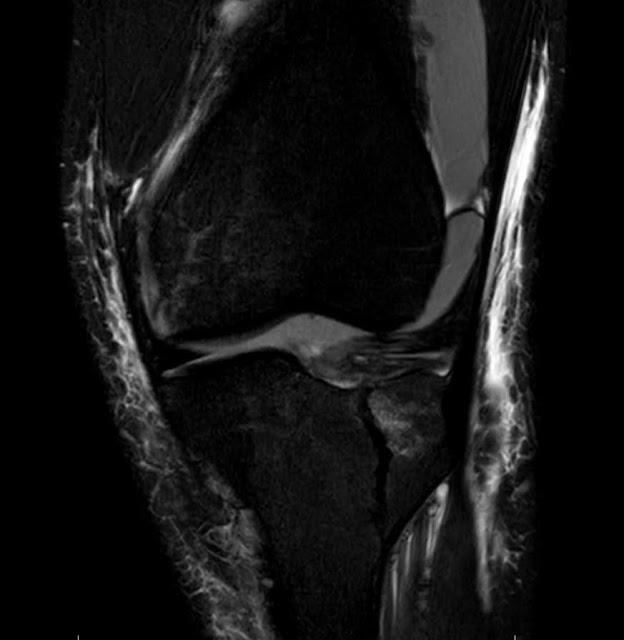

I was referred to an Orthopedic Surgeon who confirmed with MRI (imaged below) that both legs were fractured. On Thursday 08/06/2020, I went into surgery and had three screws placed in each leg, holding the fracture together to heal faster.